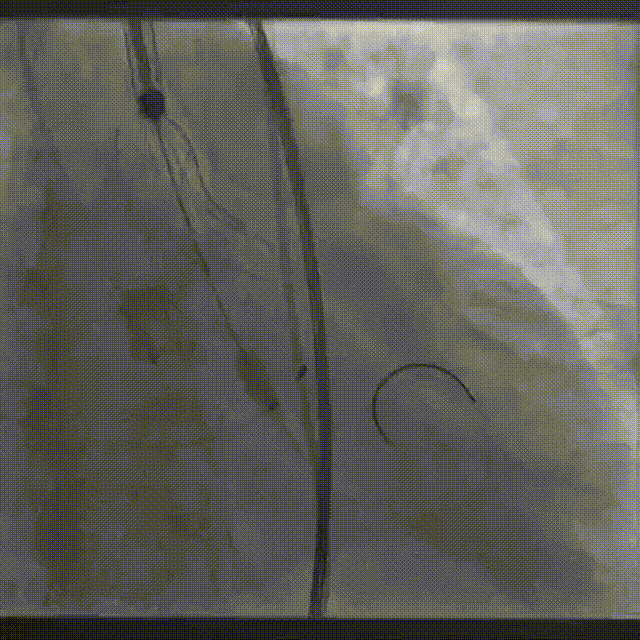

手术影像:

瓣膜逐个脱钩

完全释放后造影,膨胀不良,有漏

25mm球囊后扩

后扩后瓣膜形态良好,造影基本无漏

外周血管造影检查良好